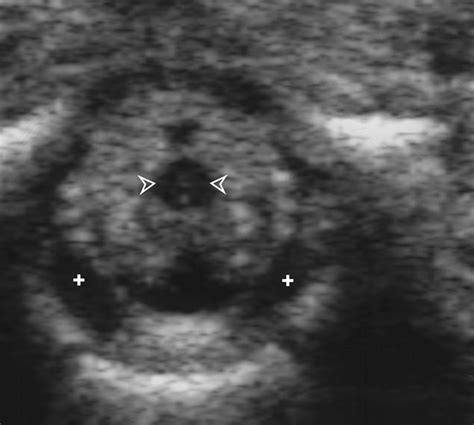

• Identify the Insertion Site: Palpate the spine to identify the L3-L4 or L4-L5 interspace, which is the most common site for lumbar puncture in neonates.

• Insert the Needle: Insert the spinal needle at a 90-degree angle to the skin, aiming towards the umbilicus. Advance the needle slowly until a "pop" is felt, indicating entry into the subarachnoid space.